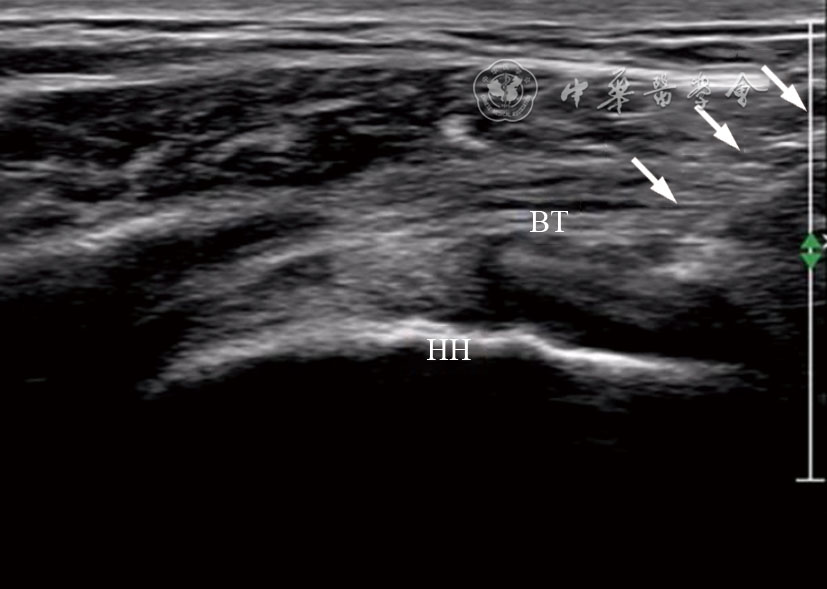

图2 超声引导肩前部肩袖间隙肩关节腔注射治疗图像 注:HH为肱骨头;BT为肱二头肌肌腱;箭头所示为穿刺针